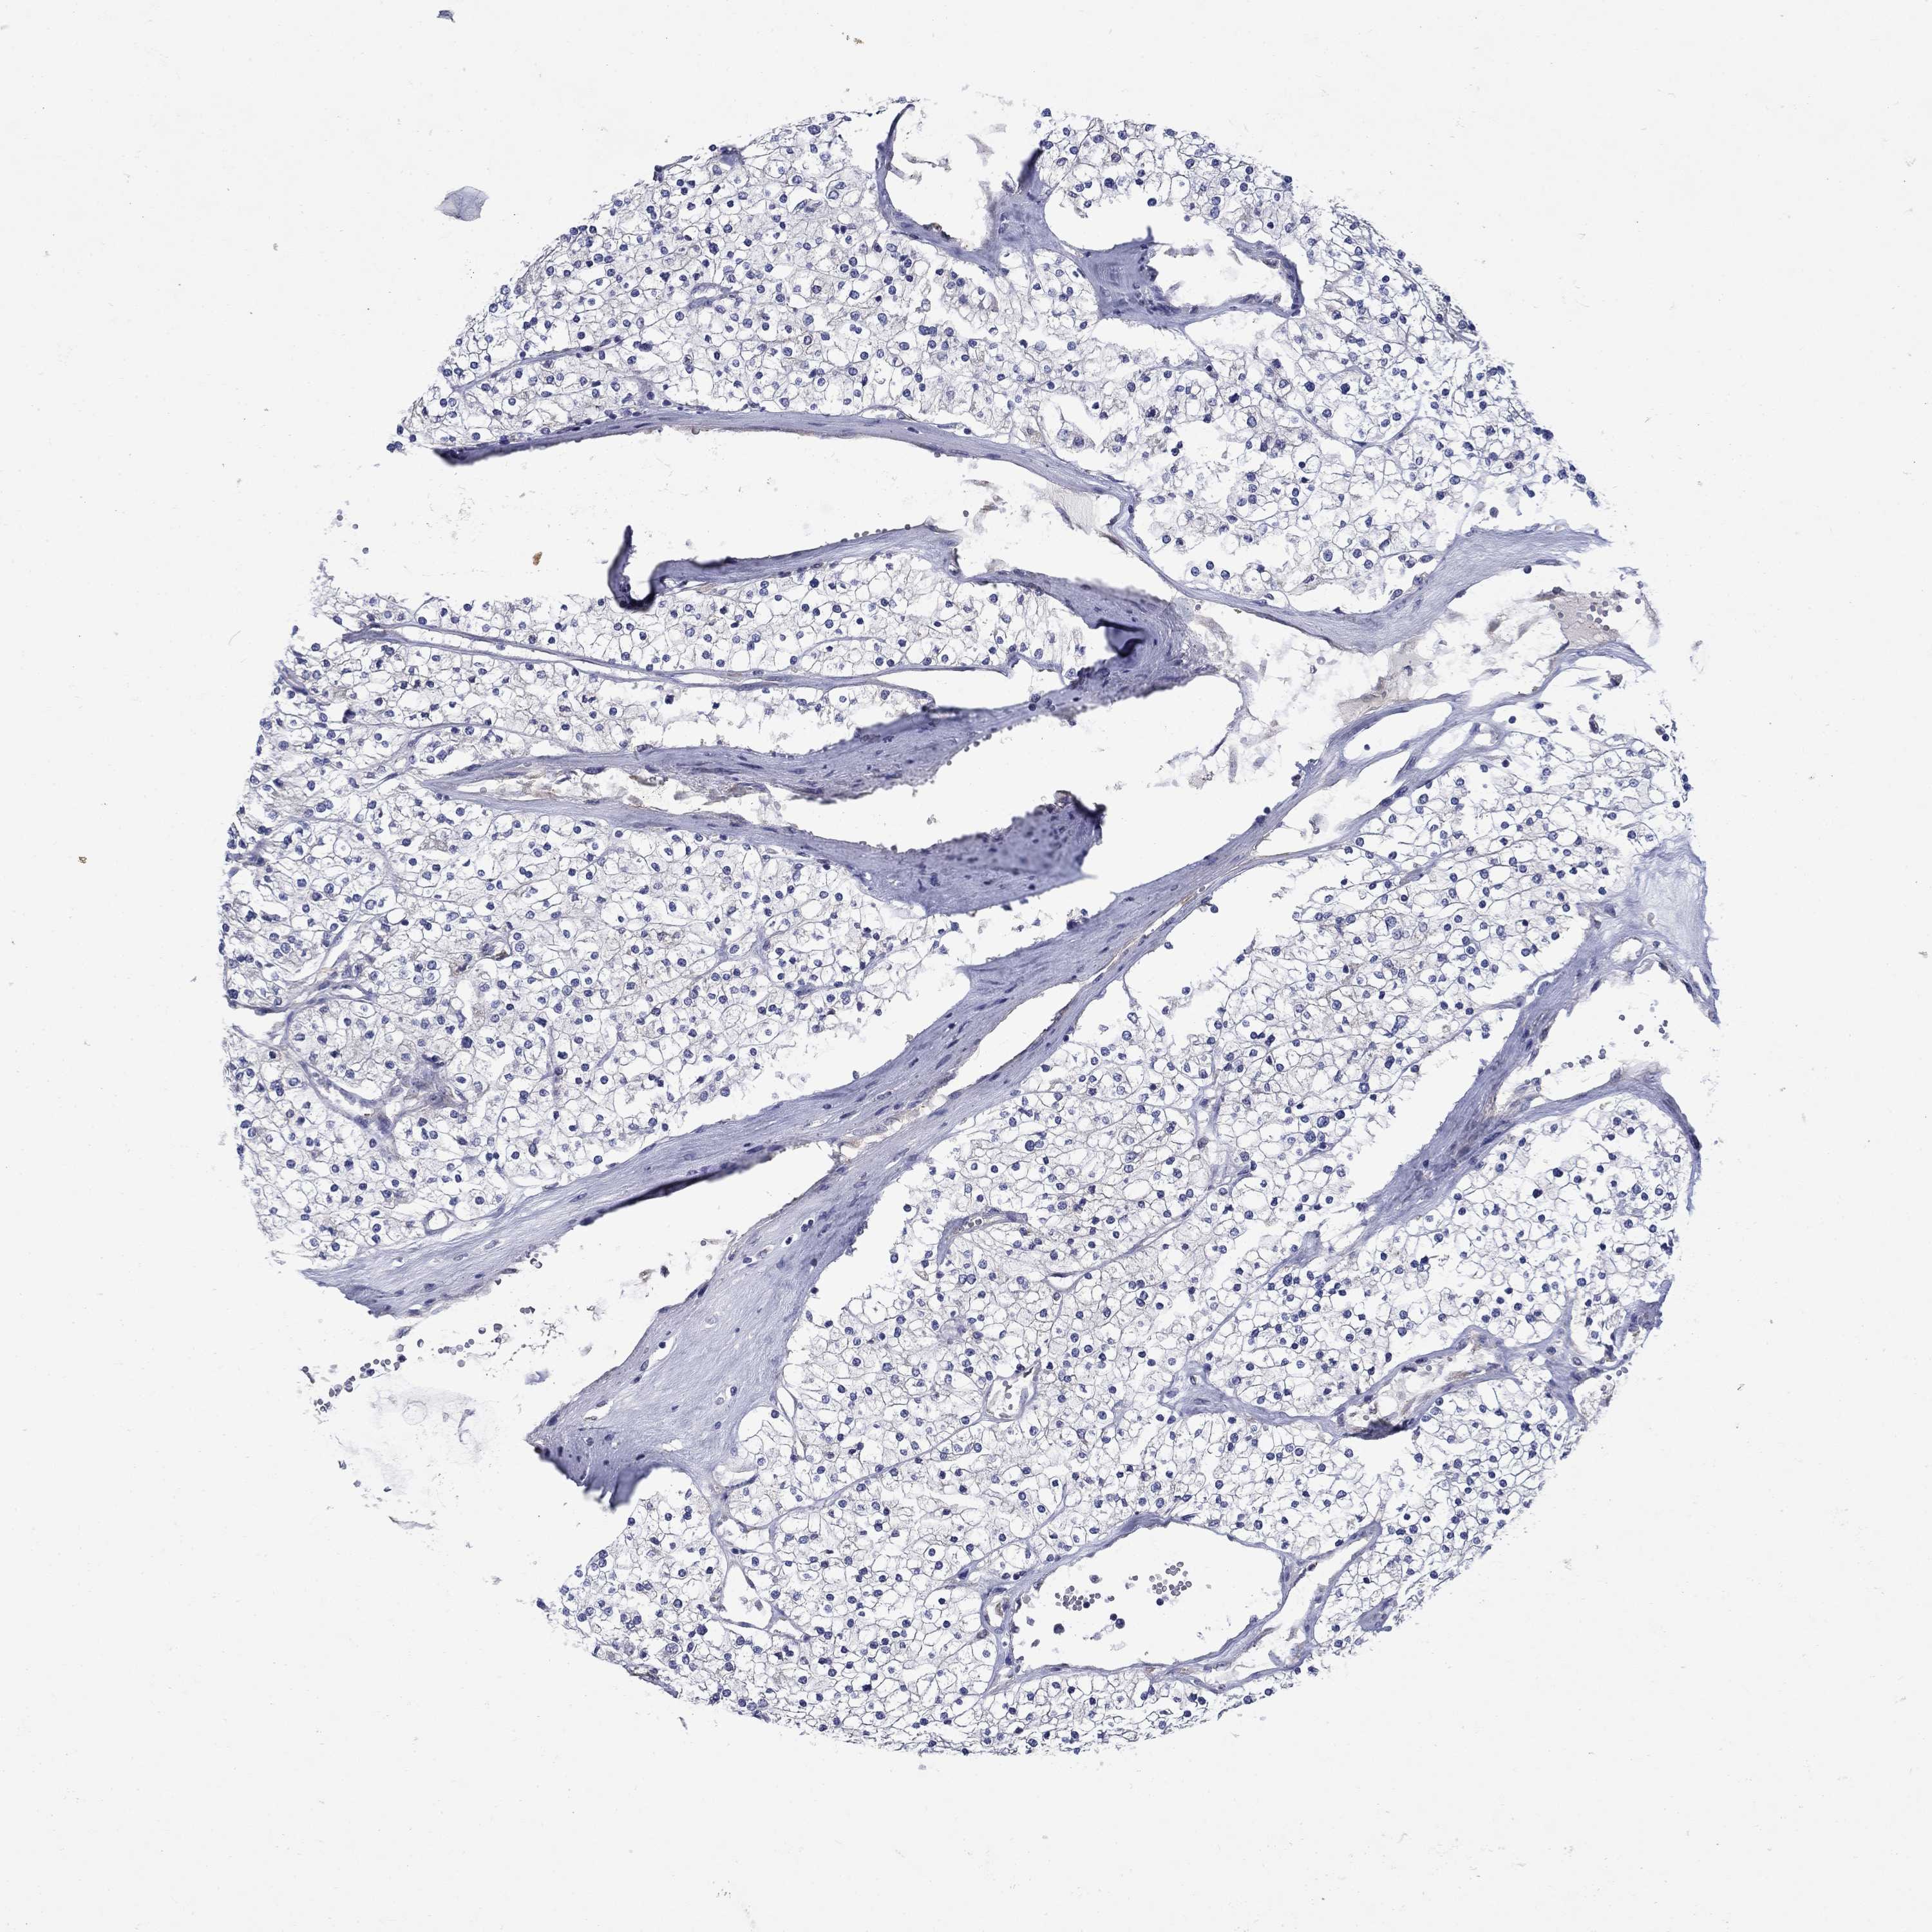

SULT2B1

KICH TCGA KIRC TCGA KIRC VALIDATION KIRP TCGA PROTEIN RCC CPTAC PROTEIN EXPRESSION